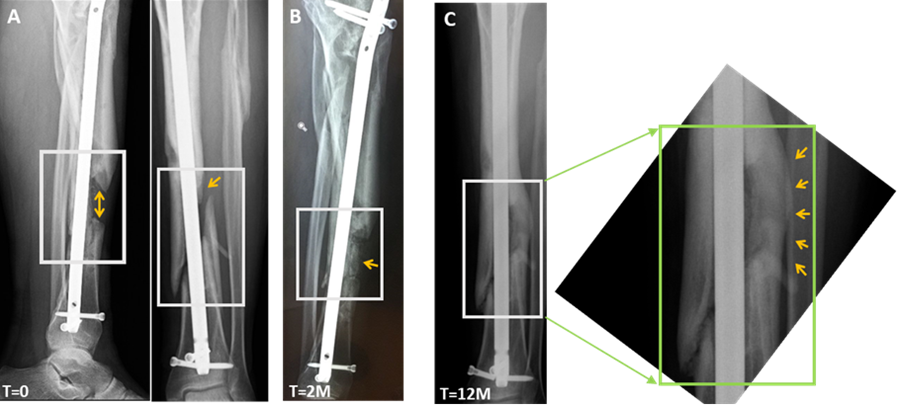

צילומי רנטגן של מטופל שהשתתף במחקר הקליני לטיפול בחסרי עצם בגפיים

(קרדיט: מתוך הדוחות הכספיים של החברה)

צילומי רנטגן של מטופל שהשתתף במחקר הקליני לטיפול בחסרי עצם בגפיים, שסבל מחסר עצם קריטי בגודל של 5 ס"מ בשוק השמאלי ואי יכולת נשיאת משקל. המטופל התלונן על כאב קבוע והיה זקוק לסיוע של קביים כדי ללכת. מצבו היה קשה, ואף נבחנה קטיעה של הגפה. זמן קצר לאחר השתלת בונופיל החולה יכול היה לעמוד על רגלו הפגועה, ללכת ללא עזרה, ואף לקפוץ, תוך כדי ירידה ניכרת בתחושת הכאב. צילומי רנטגן שצולמו לפני הטיפול ([A], T=0) וחודשיים ([B], T=2M), ו-12 חודשים לאחר הטיפול ([C], T=12M) מראים ריפוי מהיר ואיחוי של חסר העצם. אזור החסר מודגש בירוק.